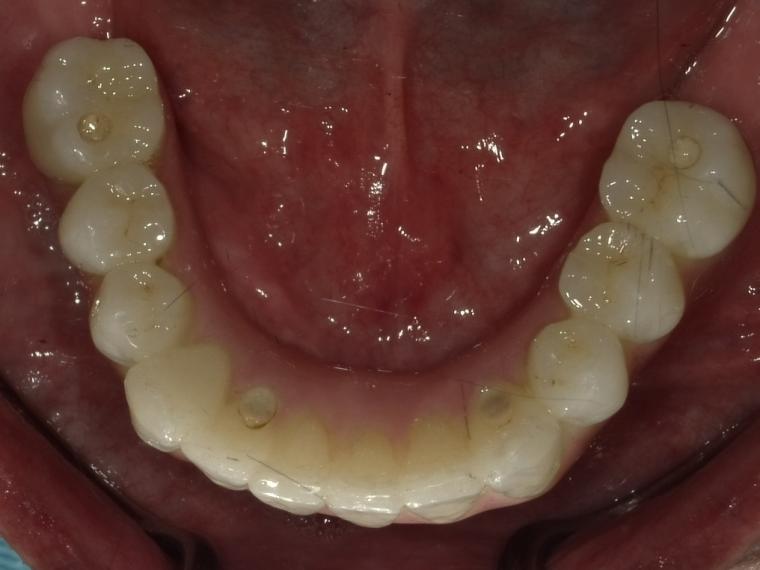

Before

62歳男性/オールオン4・6症例/インプラント埋込手術

インプラント希望でご来院された患者さんです。

美味く噛むことが出来ず美味しくお食事をしたいという主訴でご来院されました。

オールオン4・6というインプラント義歯での治療を選択されました。